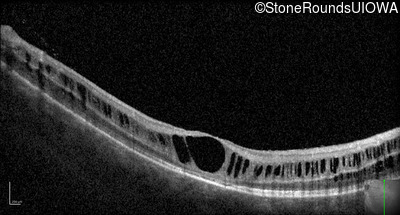

Optical Coherence Tomography - Right - 20/200

Exemplar / OCT Stack

OCT Stack

Optical Coherence Tomography - Left - 20/150